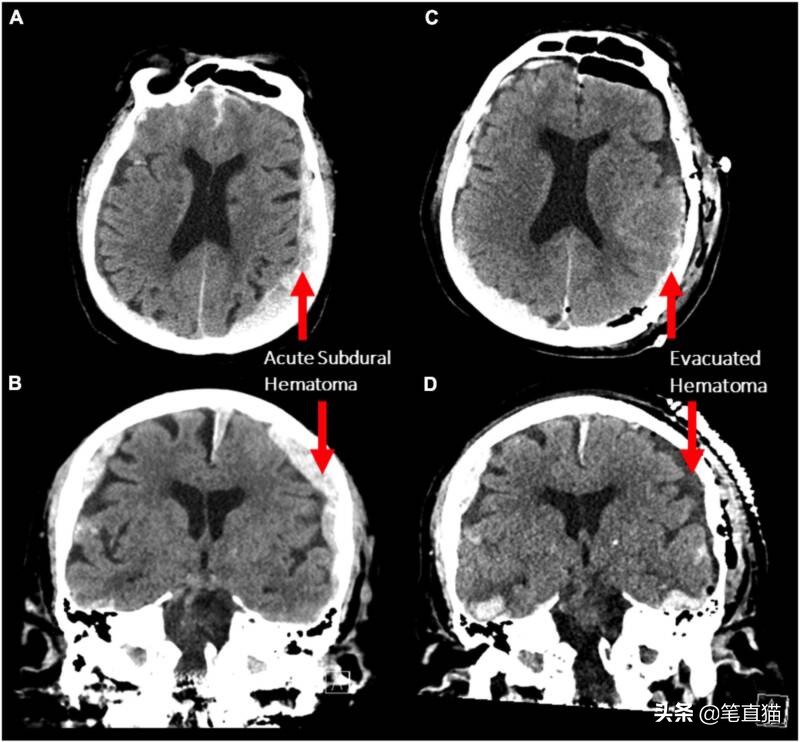

衰老神经科学前沿手术前(A 和 B)和手术后(C 和 D)患者硬膜下血肿的 CT 扫描。